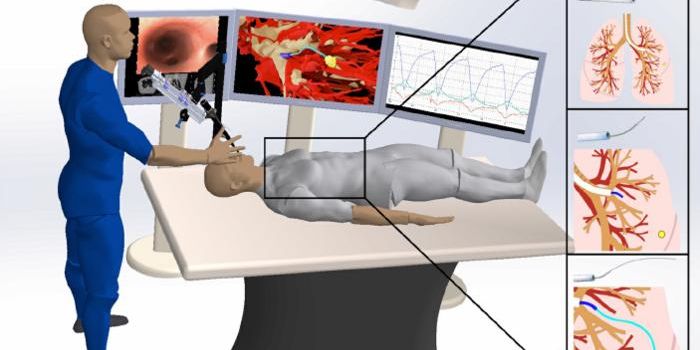

JAN 23, 2023Cell & Molecular BiologyStudies have shown that cells respond to electric fields, and electrotaxis is when cells are moving under the influence ...